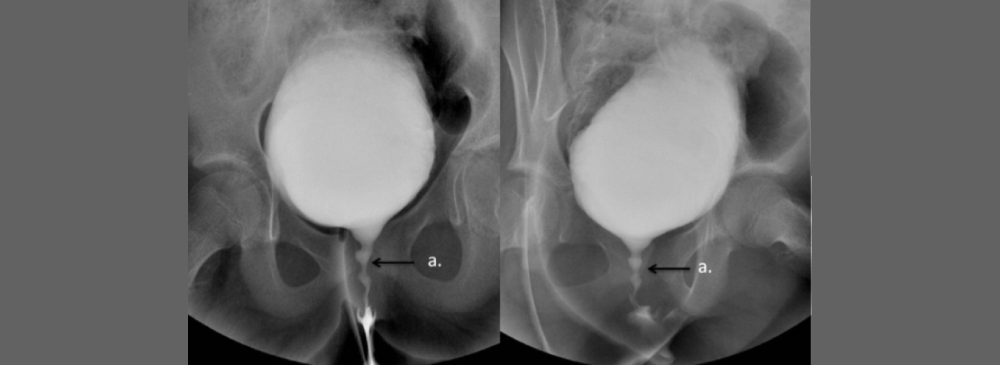

A Micturating Cystourethrogram, often abbreviated as MCU, is a specialized X-ray test designed to evaluate how well your bladder and urethra function when you urinate. Unlike conventional X-rays that take static pictures, an MCU captures a series of images in real time as the bladder fills and empties, thanks to the use of a contrast dye. This dynamic visualization helps doctors observe the flow of urine, check for abnormalities such as reflux (where urine flows backward toward the kidneys), and assess any structural blockages or narrowing that might affect urinary health.

The MCU procedure begins with the careful insertion of a thin, flexible catheter into the bladder through the urethra. This catheter allows us to fill the bladder gradually with a water-soluble contrast dye that makes the bladder and urethra visible on X-ray images. Once the bladder is adequately filled, you will be asked to urinate while a series of X-ray images are taken in rapid succession. These images provide a dynamic “movie” of the urine flow, enabling detection of abnormalities such as reflux, blockages, or structural deformities.